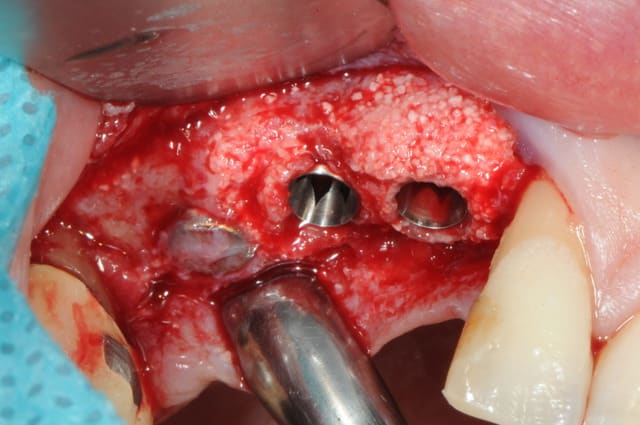

il se trouve que j'aimerais utiliser ces photos car c'est le nouveau systeme d'implants, et je n'ai encore pas d'autres cas de fracture en cours

enfin si mais pas aussi belle

j'ai donc agrandi la zone est ce qu'un pro de la photo peut faire mieux?

pour pluton, je viens de poser les implants le cas n'est pas fini